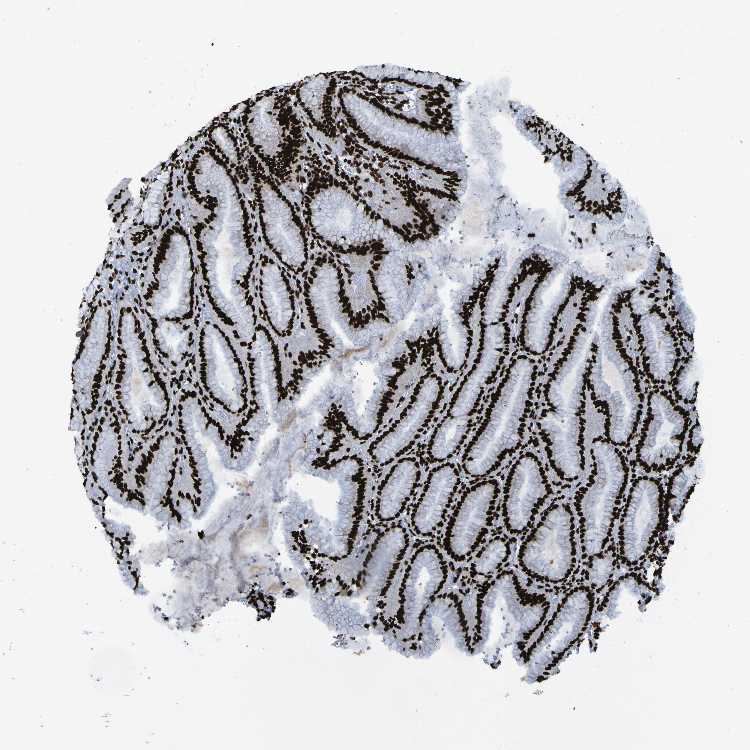

TISSUE PRIMARY DATA STOMACH Show tissue menu

STOMACH 1 - Antibody stainingi

Antibody staining in the annotated cell types in the current human tissue is reported as not detected, low, medium, or high, based on conventional immunohistochemistry profiling in selected tissues. This score is based on the combination of the staining intensity and fraction of stained cells.

Each image is clickable and will lead to virtual microscopy that enables deeper exploration of all samples and also displays staining intensity scores, fraction scores and subcellular localization as well as patient and tissue information for each sample.

Antibody HPA011384Antibody CAB012983

Glandular cells HighHigh